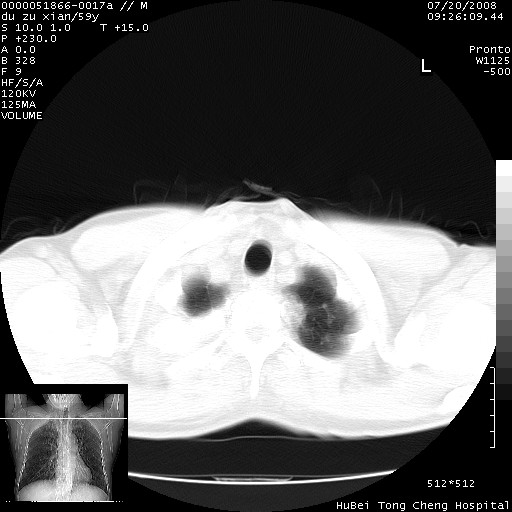

以下是引用宇宙ct在2008-8-25 23:21:00的发言:[br]右肺周围性肺癌并肋骨转移,纵隔淋巴结转移。

以下是引用zsl6918在2008-8-25 22:40:00的发言:[br]右肺周围性肺癌并肋骨转移,纵隔淋巴结转移。

以下是引用zy_zj在2008-8-26 15:24:00的发言:[br]单从病变本身,我倾向良性炎性病变,但肋骨转移了,所以说是考虑右肺周围性肺癌并肋骨、纵隔淋巴结转移可能性大。